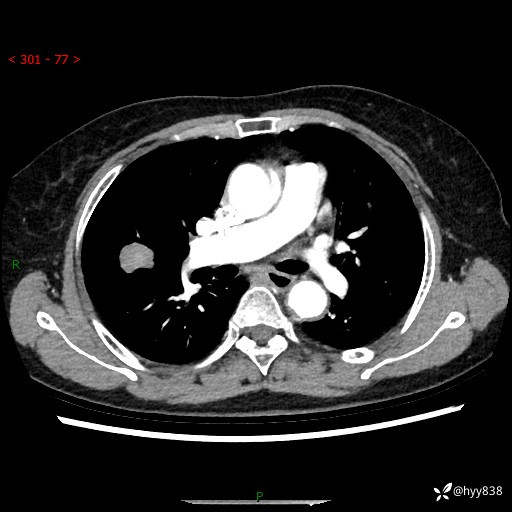

现病史:患者1月前无明显诱因出现痰中带鲜红色血丝,伴间断咳嗽,晨起明显,无胸闷、胸痛,无恶心、呕吐,无发热、畏寒,无活动后气短,无盗汗、咯血、消瘦等不适,未行诊疗。患者1天前于我院就诊,行胸部CT:右肺中叶及右肺下叶结节影,右肺上叶磨玻璃影,左肺上叶纤维灶。门诊以“咯血原因待查 肺结节”收入我科。 起病以来,患者精神、饮食、睡眠尚可,大小便正常,体力、体重未见明显改变。

胸部CT平扫+增强